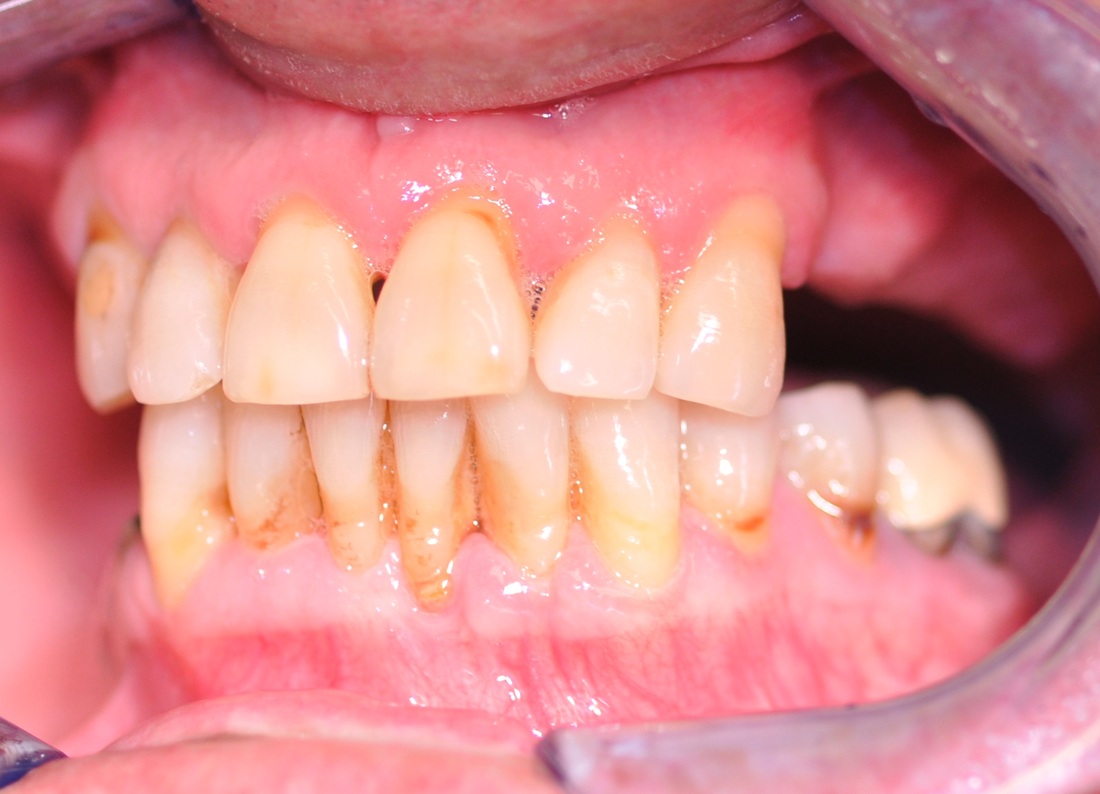

COMPREHENSIVE DENTAL REHABILITATION

A patient presented with partial teeth loss, periodontal disease, vertical bite collapse, wear on remaining teeth and smile issues.

The patient also suffered from frequent headaches, sore neck muscles, pain and clicking in both TMJs. After thorough and comprehensive evaluation- including neuromuscular diagnostic workup- a new physiological bite was established.

Missing teeth were replaced with dental implants. Teeth, damaged by bruxism (clenching and grinding), were restored with new myobite using all-ceramic veneers and crowns. During his 3-year follow-up visit the patient reported no headaches and no pain in the TMJs, improved sleep and dramatically decreased soreness of the neck muscles.